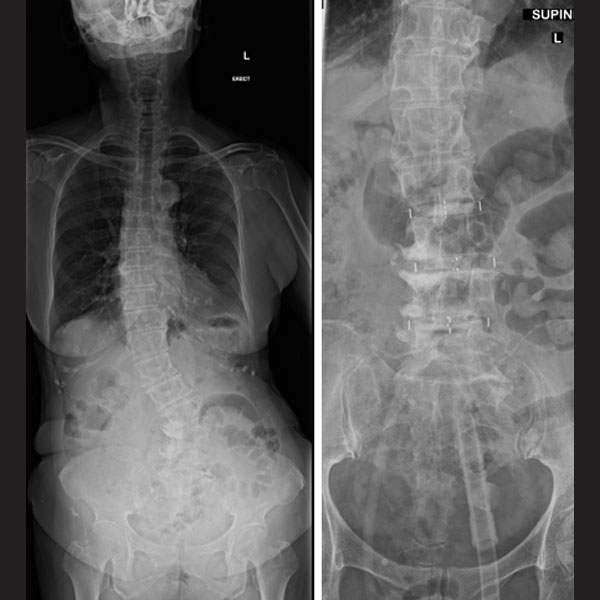

Coronal Cobb’s correction

It is well known that, degenerative lumbar deformities are often associated with coronal translation of the vertebral body and asymmetric disc space collapse. This malalignment is better suited for correction on the same plane as the deformity. This is one of the important advantages of the pre-psoas corridor as it helps to effectively correct the asymmetric disc space collapse, coronal obliquity, and lateral vertebral translation and improves the overall C7-CSVL balance.

Note the coronal imbalance in the patient. Fusion performed using the pre-psoas approach, showing the vertebral bodies almost horizontal with a good correction of the coronal Cobb’s angle.